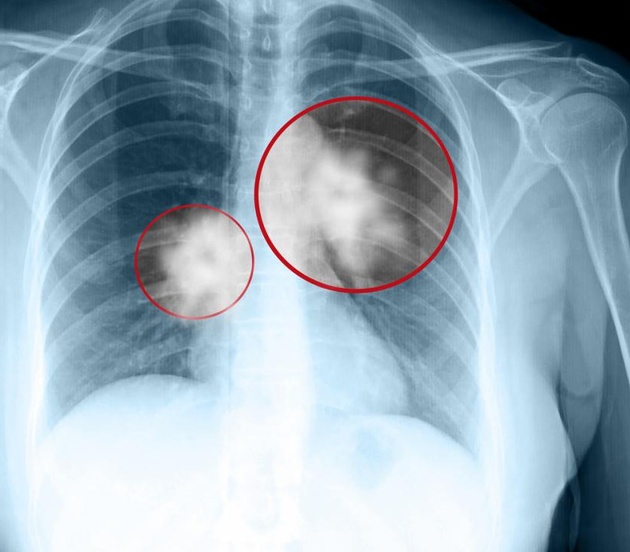

Cuba đã phát triển thành công và sở hữu một loại vắc-xin chống ung thư phổi. Mang cái tên Cimavax, nó có thể biến ung thư phổi giai đoạn cuối thành một bệnh mãn tính có thể kiểm soát.

Thay vào đó, Cimavax thúc đẩy cơ thể người bệnh sản xuất kháng thể chống lại một hooc-môn tăng trưởng biểu bì. Loại hooc-môn này thúc đẩy sự tăng trưởng tế bào, nhưng mặt khác khiến khối u lớn lên và mất kiểm soát. Kiểm soát được loại hooc-môn này, Cimavax có thể ức chế sự phát triển của ung thư phổi, hạn chế sự di căn của nó và biến ung thư chỉ còn là một bệnh mãn tính để điều trị.